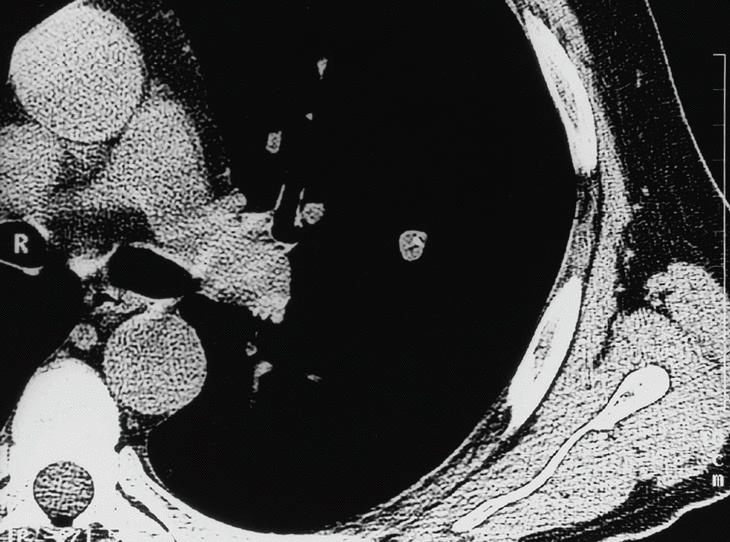

Fig. 8. Lesión pulmonar en el lóbulo superior izquierdo de 1,6 cm de diámetro máximo, contornos mal definidos, bordes espiculados, colas pleurales y signo del broncograma aéreo. Lesión de características radiológicas malignas.

Tablas